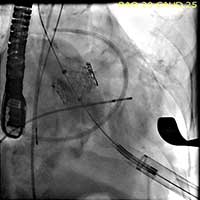

- The valve is deployed in position during direct fluoroscopic visualization (Figure 6) with another brief period of rapid ventricular pacing to reduce ejection. Respirations are also suspended during this period to limit the movement within the thoracic cavity and optimize visualization. Clear communication is critical during this brief period of the procedure and so one person commands the timing of each step of the procedure in a standard clear format.

Figure 6. The valve is deployed in position during direct fluoroscopic visualization with a brief period of rapid ventricular pacing to reduce ejection.